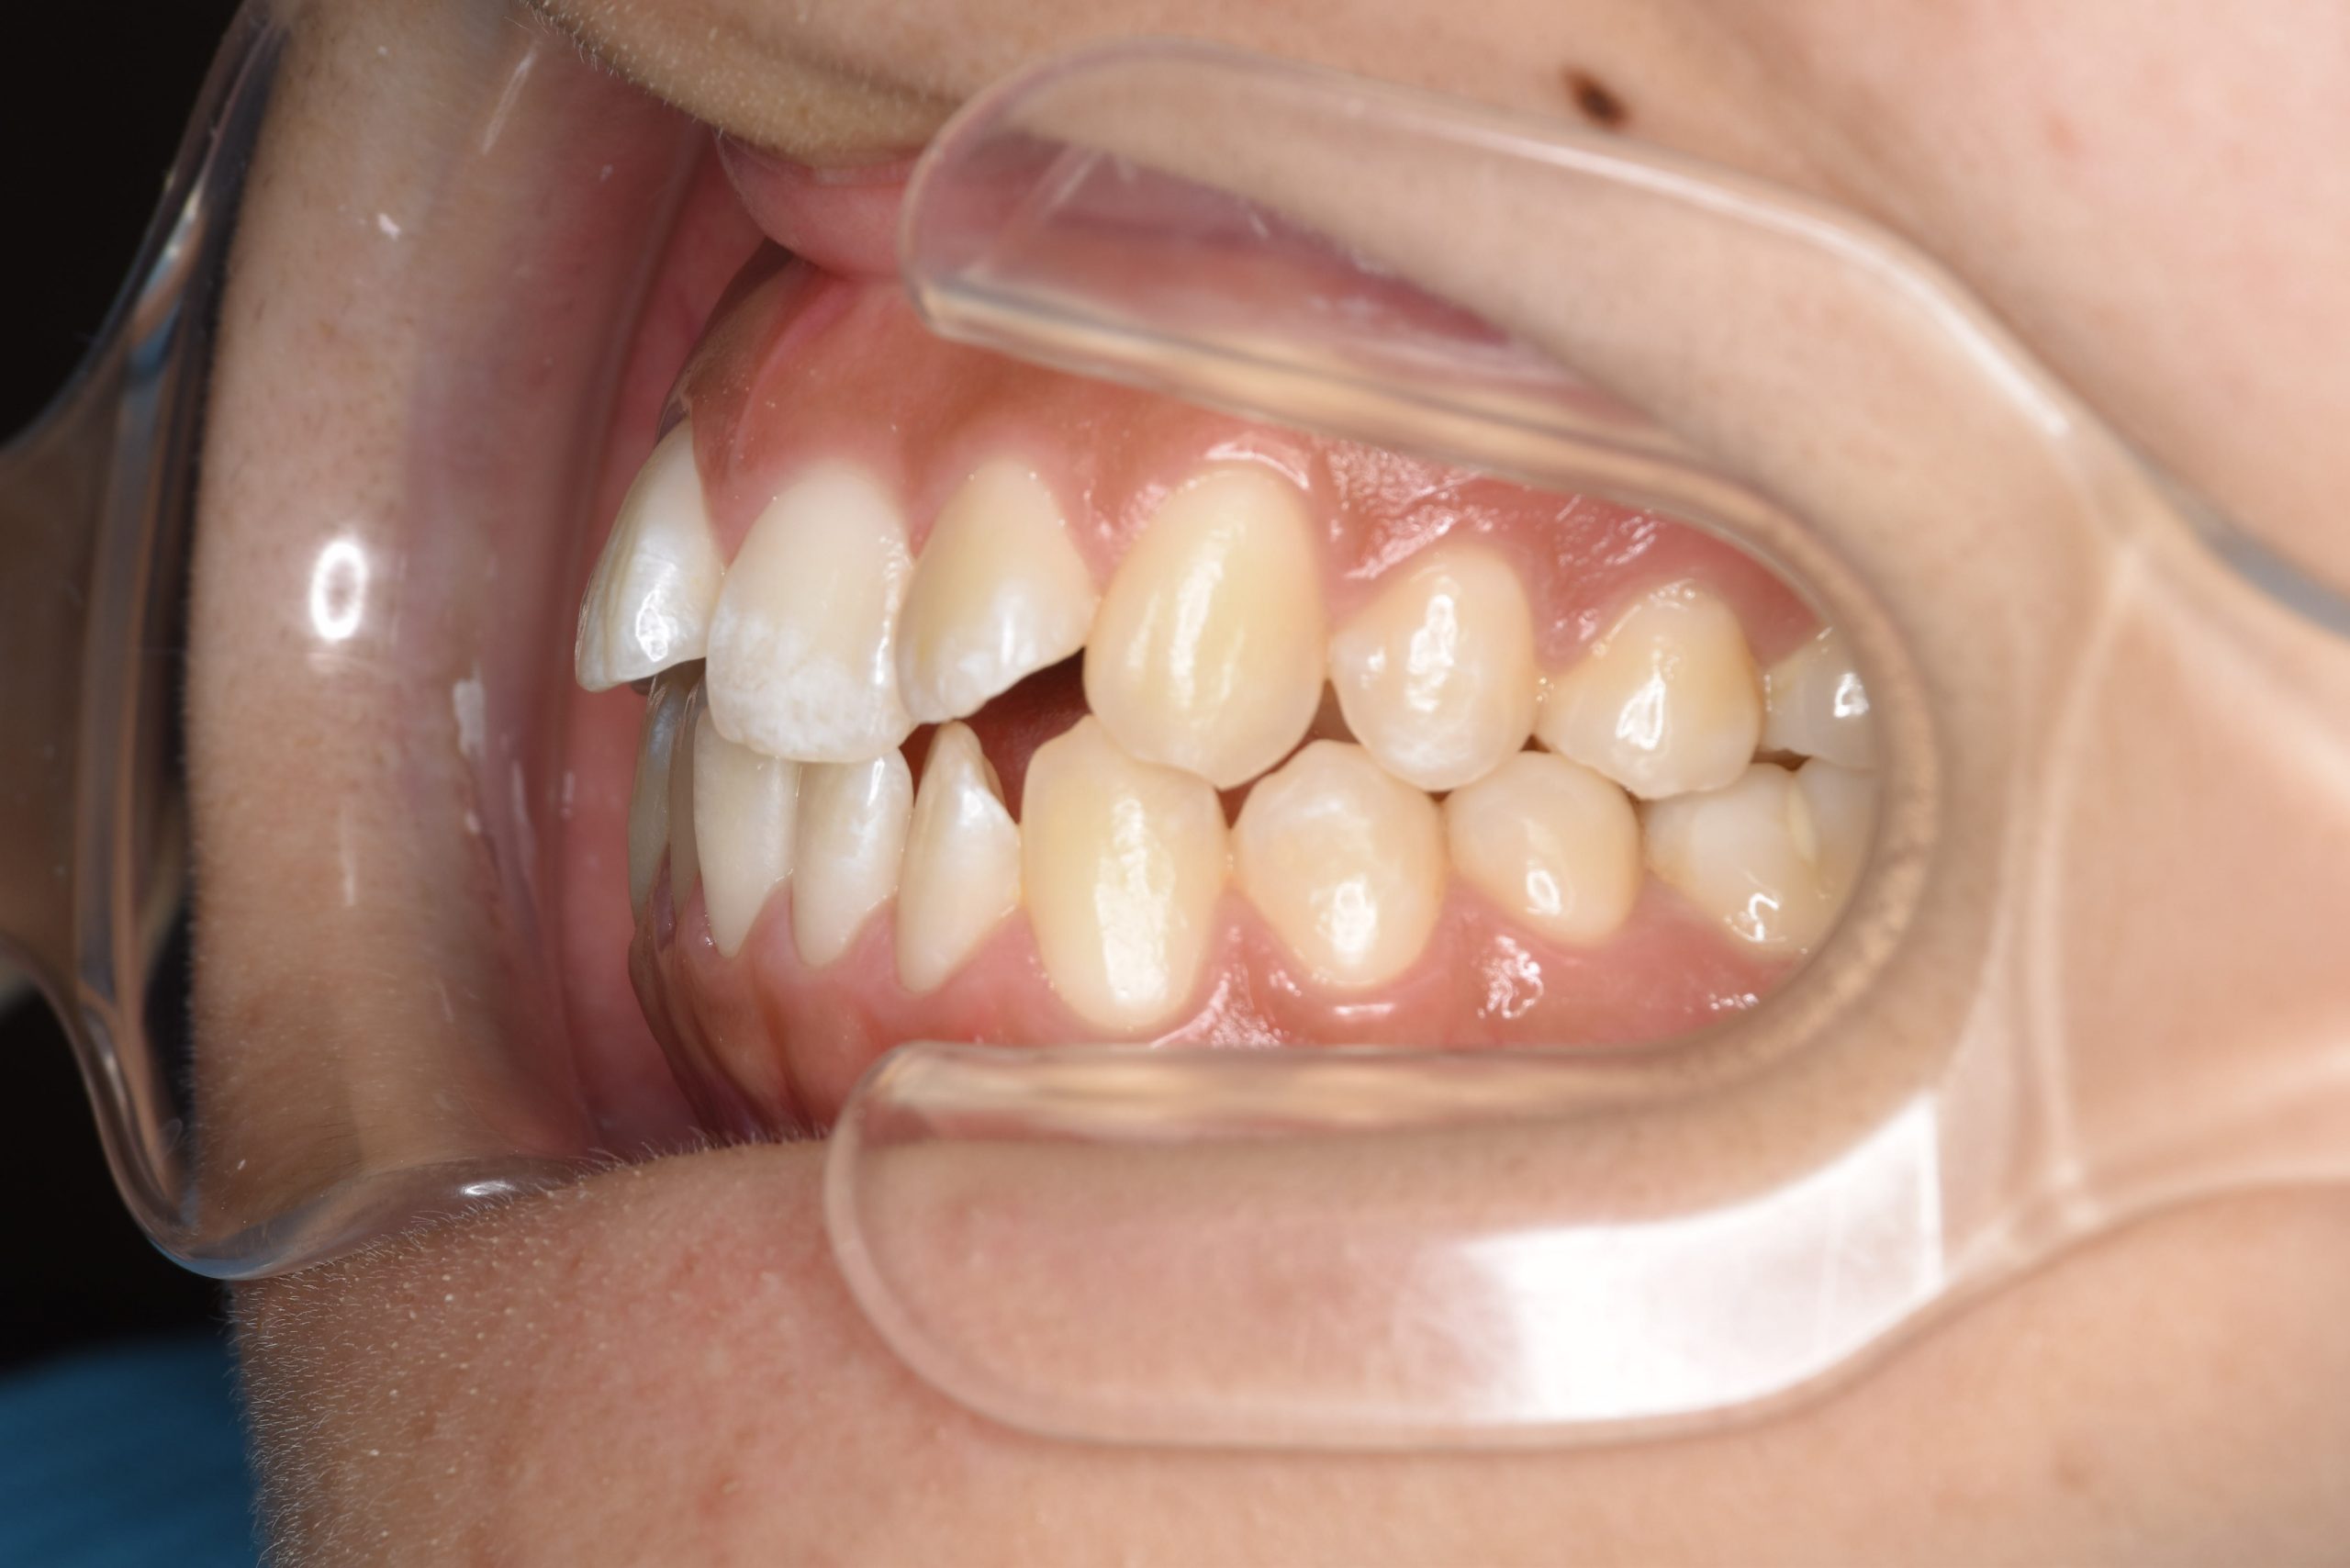

ビフォー

アフター

主訴 前歯の歯並び

施術内容 成人矯正1期治療

治癒期間 1年2か月間

費用 954,800円(税込)